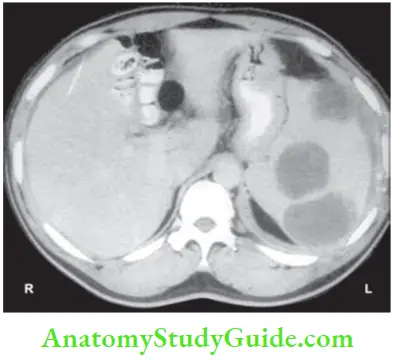

Most of these injuries are diagnosed by CT scan today (CT classification is given).

- CT scan is more reliable. It should be used in cases of doubtful diagnosis and stable patients.1 It also rules out hollow viscus perforation, pancreatic injuries, etc.

Among neoplasms, lymphoma is the most common cause of enlargement of spleen. Spleen used to be removed as a part of a staging laparotomy. Now, it is very rarely removed. Patients with large spleen of chronic myeloid leukaemia, Gaucher’s disease and hairy cell leukaemia (details later) will also benefit from splenectomy.

- Splenectomy is indicated in cases of diagnostic difficulties and in very large spleens.